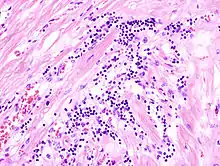

Acute myocardial infarction

Der Myokardinfarkt muss mind. 6 - 12 Stunden überlebt werden, bevor er morphologisch sichtbar wird!

Mikro: Koagulationsnekrose, Einblutungen. Die Myozyten zeigen eine verstärkte Eosinophilie und Kontraktionsbanden quer durch die Herzmuskelfasern. Typische Zellparameter wie Querstreifung, Zellkerne und Zellgrenzen gehen verloren. Das Infarktareal wird von einer Hyperämischen/hämorrhagischen Randzone begrenzt. Im Verlauf zunehmende leukozytäre Demarkation und Phagozytose des nekrotischen Gewebes, sowie Einwanderung von Fibroblasten mit Ausbildung eines narbigen Ersatzgewebes.

Makro: Lehmfarbene Abblassung mit hyperämischem/hämorrhagischem Randsaum.

![]() Akuter Myokardinfarkt, H&E. |